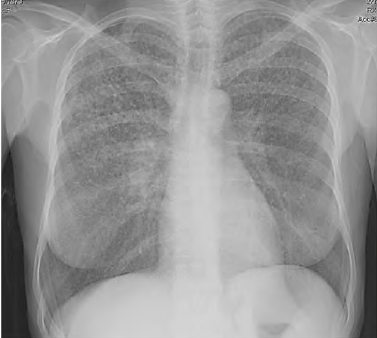

Uma paciente de 45 anos de idade compareceu, acompanhada pela filha, a uma consulta ambulatorial. Queixa-se de perda de peso (em torno de 4 kg nos últimos seis meses), febre vespertina e fadiga há mais de 20 dias. Observe que tem trabalhado muito, tem uma fadiga crônica e acha que iniciado os sintomas após exposição à chuva e o frio quando voltava do trabalho para casa. Ela informa que é etilista social e tabagista (15 cigarros / dia), e alguns exames laboratoriais como hemograma, eletrólitos, função hepática e renais normais. Os raios X de tórax estão representados na imagem a seguir. O resultado do PPD e o lavado brônquico são negativos.

Com base nesse caso clínico, na imagem apresentada e nos conhecimentos médicos correlatos, julgue o item a seguir.